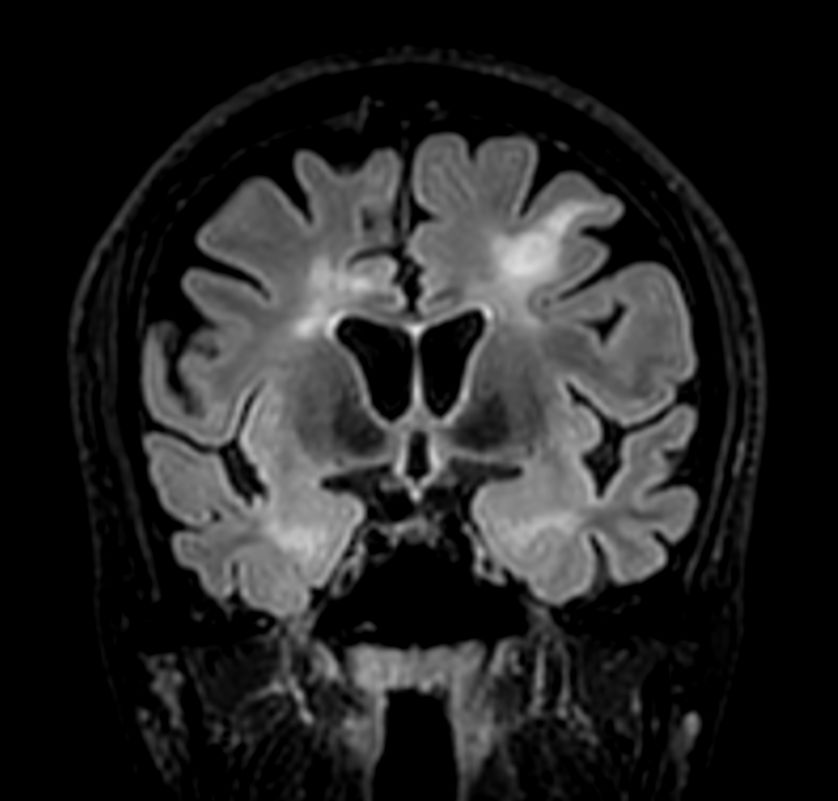

T2w TSE MultiVane XD